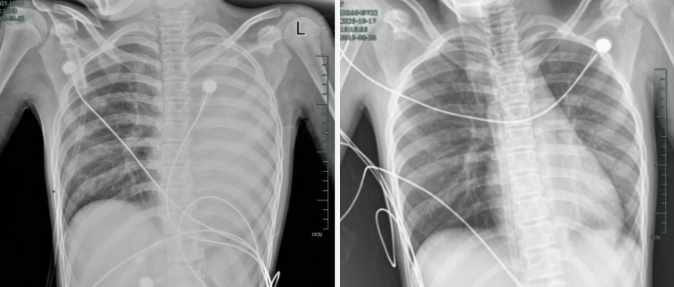

孩子感冒咳嗽看似常见,可12岁女孩笑笑(化名)的经历却让人感到后怕——仅发热1天,左肺就变成了 “白肺”,呼吸急促到无法平躺,血氧饱和度勉强维持在90%左右,情况十分危急!治疗前后影响对比,左肺从“白